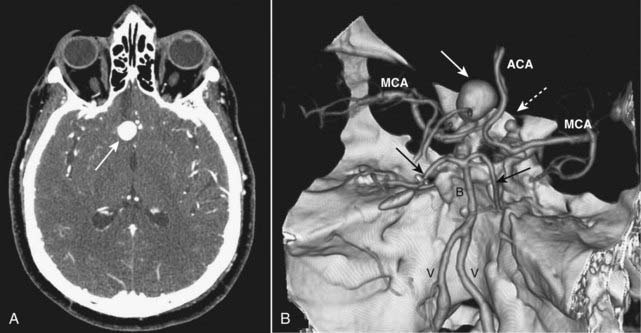

image

Figure 25-20 Berry aneurysm, axial CT and 3-D reconstruction.

A, There is a 2 cm focal outpouching of contrast in the region of the right internal carotid artery (ICA) on this contrast-enhanced CT of the brain (solid white arrow). This is consistent with an aneurysm. B, A 3-D reconstruction of the circle of Willis from a CT-angiogram demonstrates the aneurysm arising from the supraclinoid segment of the right ICA (solid white arrow) and another smaller aneurysm arising from the supraclinoid segment of the left ICA (dotted white arrow). V = vertebral artery; B = basilar artery; MCA = middle cerebral arteries; ACA = anterior cerebral arteries; solid black arrows point to posterior cerebral arteries.